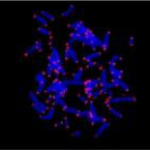

- 着丝粒FISH探针测到染色体组着丝粒部位的异常,例如三体性、多体性以及着丝粒的断裂。 货号 英文名称 规格 F3003 Cent-Cy3 5nmole F3006 Cent-FAM 5nmole 白血病 淋巴瘤 移植相……阅读更多:着丝粒FISH探针

- PNA端粒 FISH探针肽核酸 (PNA, peptide nucleic acid)是一种全新的DNA类似物,可以识别并结合 DNA或 RNA序列,形成稳定的双螺旋结构。由于PNA不带负电荷,……阅读更多:PNA端粒 FISH探针